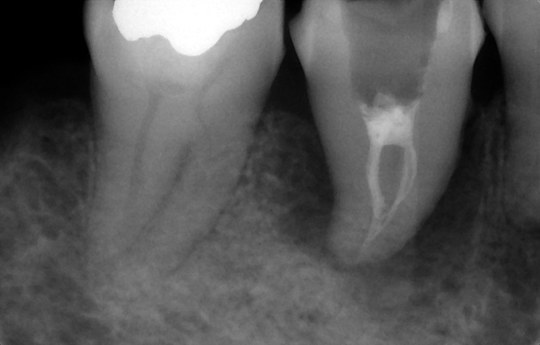

虫歯で歯が割れて周囲に強い歯周病

親知らずを移植し根管治療中

※現在治癒を経過観察中